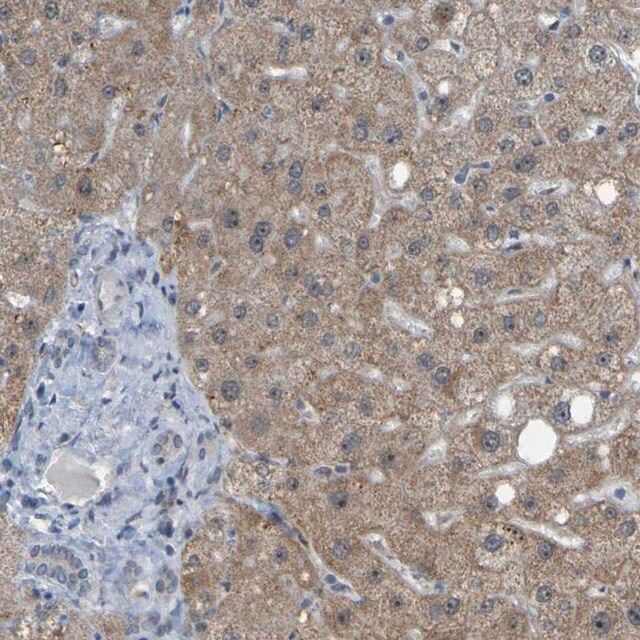

Anti-CDK1 antibody produced in rabbit, a Prestige Antibody, is developed and validated by the Human Protein Atlas (HPA) project (www.proteinatlas.org). Each antibody is tested by immunohistochemistry against hundreds of normal and disease tissues. These images can be viewed on the Human Protein Atlas (HPA) site by clicking on the Image Gallery link. The antibodies are also tested using immunofluorescence and western blotting. To view these protocols and other useful information about Prestige Antibodies and the HPA, visit sigma.com/prestige.

- IHC tissue array of 44 normal human tissues and 20 of the most common cancer type tissues.

| technique(s) | immunoblotting: 0.04-0.4 μg/mL immunofluorescence: 0.25-2 μg/mL immunohistochemistry: 1:200-1:500 |